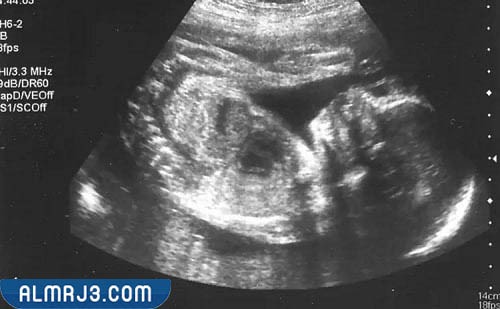

شكل الجنين في الشهر الرابع بالسونار

يظهر في الفحص بالسونار الجنين في الشهر الرابع من الحمل على النحو الذي سنذكره في السطور التالية والواضح في صورة السونار الملحقة:

- يغطي رأسه شعر خفيف جدًا.

- كافة أطراف الجنين تكون قد تشكلت، وبدأت في اتخاذ شكلها الطبيعي الدائم.

- أظافر الجنين تكون قد نمت وغطت أصابع يديه وقدميه.

- تظهر أعضاء الجنين التناسلية بوضوح مما يمكن الطبيب من إخبار الأم بجنس جنينها.

- رأس الجنين تكون كبيرة نسبيًا بالنسبة لحجم جسمه، لكن سيستمر باقي جسم الجنين في التطور إلى أن يصبح حجم رأسه مناسبًا لحجم جسمه.

- تبدأ ملامح وجه الجنين في الظهور بشكل واضح.